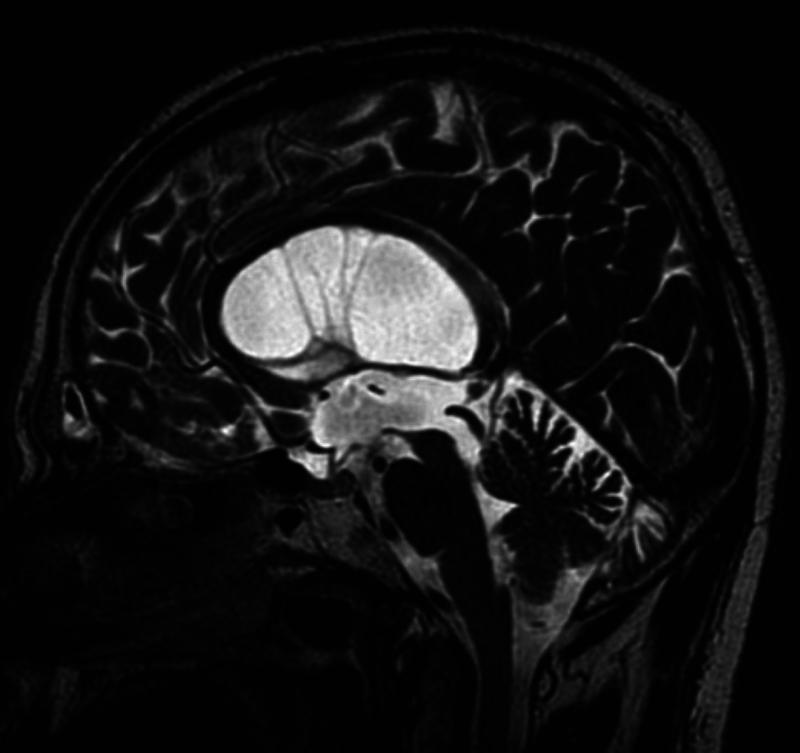

Unreliable sagittal T2-weighted flow void MRI in diagnosing third ventriculostomy: a case of long-standing obstructive hydrocephalus. Illustrative case.

The authors report an illustrative case of pseudo-STV in a 67-year-old man who presented with long-standing obstructive triventricular hydrocephalus. Despite the neuroimaging findings suggesting STV, endoscopic third ventriculostomy showed an intact floor of the third ventricle.

The authors demonstrate the potential for imaging to be misleading in the diagnosis of STV. A flow void artifact on sagittal T2-weighted sequences of the floor of the third ventricle may reflect the fast motion of a thin third ventricular floor or CSF passage through the foramen of Monro rather than flow void through a patent stoma. Endoscopic exploration remains the gold standard for confirming the presence of a ventriculostomy, but other noninvasive tools may help differentiate real CSF intraventricular motion. Dimensional phase-contrast velocity mapping like time-SLIP (arterial spin labeling) MRI could allow the differentiation of flow artifacts caused by the rapid motion of the pulsating floor of the third ventricle from a true ventriculostomy. https://thejns.org/doi/10.3171/CASE2531.